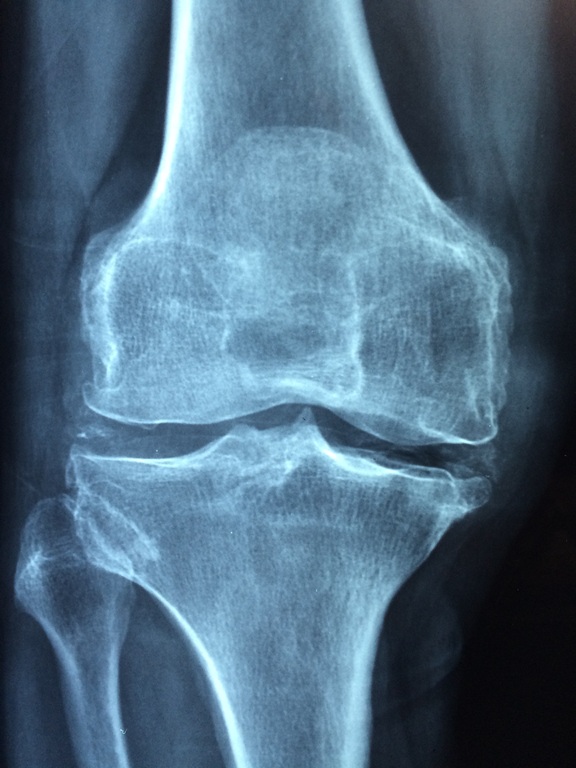

3. 관절염

관절염은 50대 이상에서 흔히 나타나는 질병으로, 통증과 불편함을 유발합니다. 퇴행성 관절염이 가장 일반적입니다.

• 원인: 노화로 인한 관절의 퇴화, 체중 증가, 부상 등이 원인으로 작용합니다.

• 예방 방법: 규칙적인 운동을 통해 근육을 강화하고, 체중을 관리하여 관절에 가해지는 부담을 줄이는 것이 중요합니다. 스트레칭과 저강도 운동이 효과적입니다.